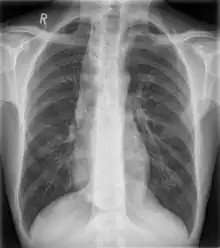

Some mediastinal structures on a chest radiograph.